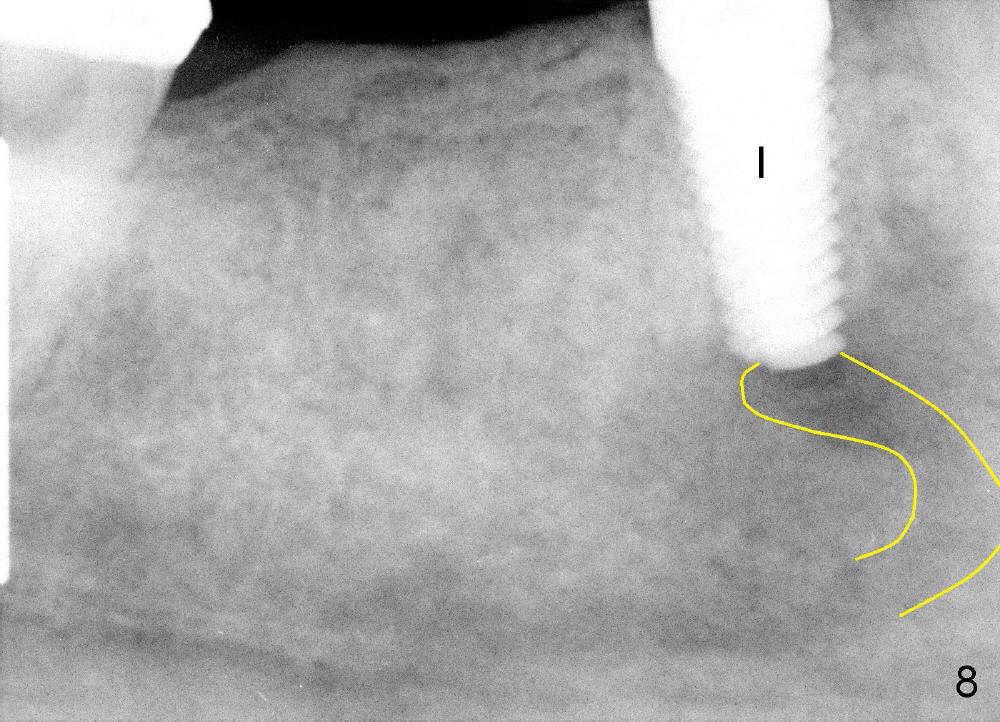

Osteotomy is created by using taps manually. There is no engagement of 5x20 mm tap (at the depth of 17 mm) with the socket. When a 6x20 tap (17 mm deep) is inserted, it is stable (Fig.7). In order to engage better, a 6x17 tapered drill is used (force applied lingually). Finally 6x17 mm implant (Fig.8 I) is inserted with torque more than 60 Ncm. The opening of the socket is obliterated by the large diameter implant, as evident by Fig.9,10 (2 weeks postop). There is no sign or symptom of paresthesia intra or post-op.